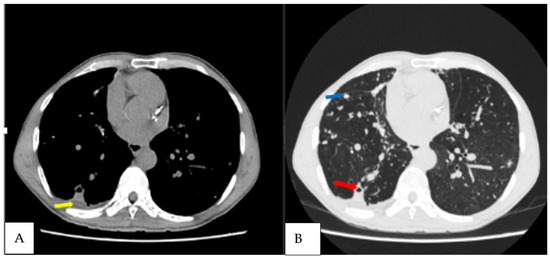

| 50 | M | Haemoptysis, cough, fatigue | Positive | A. fumigatus | Cavities, intracavitary material, pleural thickening adjacent cavity, pericavitary fibrosis, nodules, bronchiectasis | 30, 15, 49 |